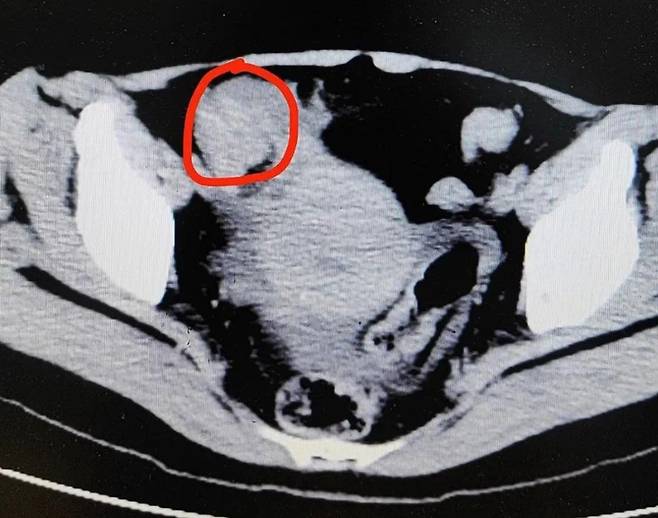

항저우 제1인민병원 의료진은 일련의 검사를 실시한 뒤 소장이 막힌 사실을 발견했다. 의료진은 장폐색일 가능성이 높다고 판단했다.

![감과 털게를 먹었다가 소장에 결석이 생긴 여성. [항저우제1인민병원]](https://img2.daumcdn.net/thumb/R658x0.q70/?fname=https://t1.daumcdn.net/news/202411/13/ned/20241113141301810hphr.jpg)

수술 중에는 소장에서 단단한 결석이 발견됐다. 가로 길이 4cm, 세로 길이 3cm인 돌이 장을 막고 있어 음식물이 정상적으로 통과하지 못하는 상태였다. 의료진은 결국 펑씨의 소장을 일부 절제했다.

의료진은 결석 발생 원인이 펑씨가 섭취한 음식에 있다고 봤다. 감은 탄닌산 함유량이 높은 과일로 이 탄닌산은 단백질과 잘 결합하는 특징이 있다. 감을 고단백 식품과 함께 먹으면 결석을 유발할 수 있다.